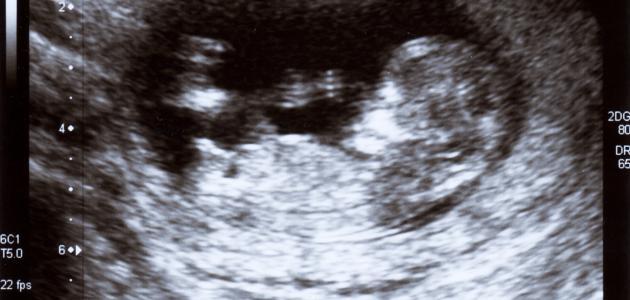

يَحدث الحمل عند اختراق الحيوان المنوّي للبويضة؛ فتُغلق البويضة ويقوى جدارها، وتتكوّن البويضة المُخصّبة؛ حيث تقوم البويضة بالتدحرجِ ثمّ الالتصاق بجدار الرحم ليتكوّن هنا الحمل، ولكن الجنين هنا لم يتكوّن بعد؛ وهو عبارةٌ عن نقطة دمٍ لا نبض ولا حركة، ولكن هناك أعراض قد توضّح لنا وجود الحمل.[١]